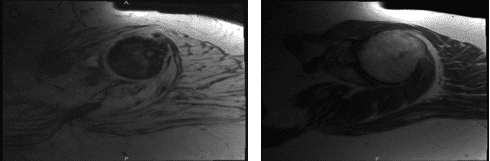

MRI Clavicle has been done and presented in the office. Acromion and bursa: The acromion has a curved configuration (type II). Moderate degenerative changes are present at the acromioclavicular joint. A small amount of fluid is present in the subacromial/subdeltoid bursa.

Rotator cuff tendons: Supraspinatus tendinosis present with high-grade partial-thickness articular sided tearing and a full-thickness component involving the anterior 2.2 cm of the distal supraspinatus tendon.

Infraspinatus tendinosis is present with high-grade partial-thickness articular sided tearing. Subscapularis tendinosis is also present with partial tearing at its insertion. Biceps tendons: There is no visualization of the long head of the biceps tendon, consistent with a complete tear and distal retraction.

Cartilage and labrum: Superficial cartilage irregularity is present in the glenohumeral joint. Degenerative tearing of the posterosuperior glenoid labrum is present. Bone marrow:

Subchondral cyst formation is present on the posterior aspect of the greater tuberosity. The bone marrow signal is overall age appropriate.

There is no evidence for significant lymphadenopathy in the visualized portions of the axilla. No asymmetric rotator cuff muscle atrophy is present. We decided to do another MRI to run more tests about her shoulder.

MRI first result

MRI second result